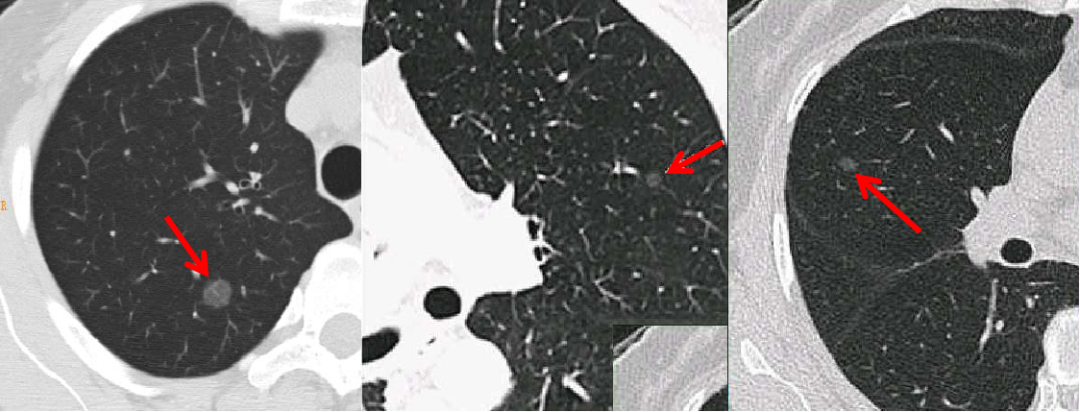

实性结节:

磨玻璃结节:

部分实性结节:

肺癌高危结节